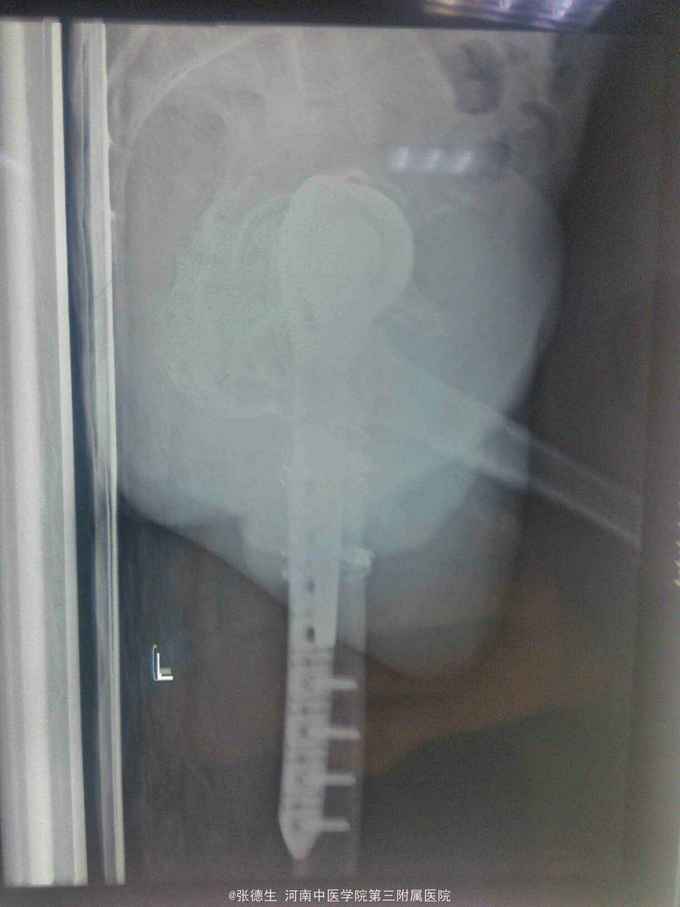

右股骨假体周围骨折 切开复位锁定板加扎带内固定术

假体周围骨折手术相对复杂,必要考虑假体是否松动或磨损,如果有要考虑假体翻修,翻修过程当中应考虑骨缺损等。本病例术前准备了全髋翻修,但术中发现假体完好,股骨柄与大小转子处无明显松动,即时给予复位锁定板加扎带固定。